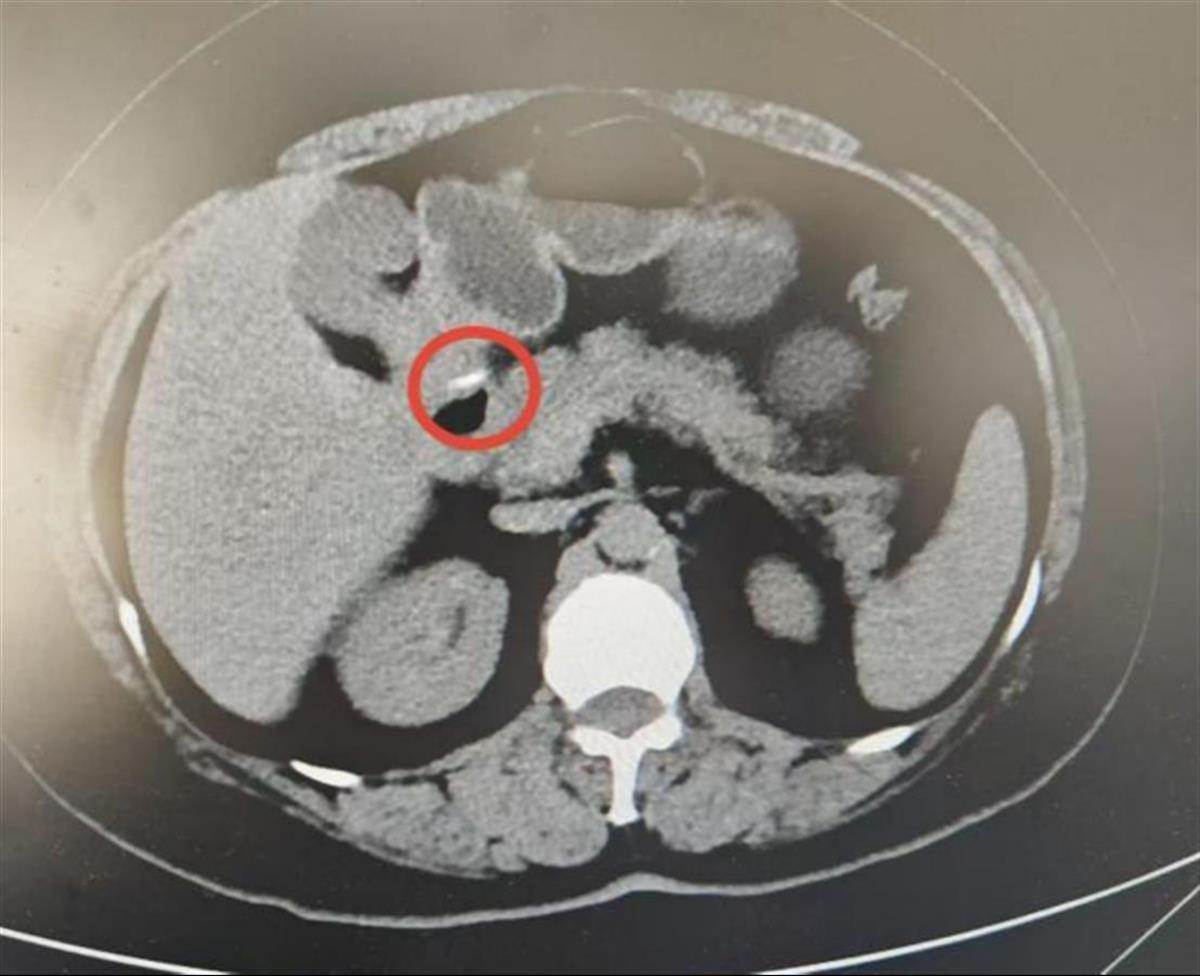

一个月前,60岁的王女士(化名)在吃饭时不慎误吞了鱼刺,她连吞了几口饭,试图将卡住的鱼刺咽下去,直到喉咙没有异物感。一周后,她突然出现剧烈腹痛、发热等症状,于是来到协和医院就诊。经腹部CT检查发现,有一根刺状条形异物穿透了胃后壁,部分位于壁外,显然是出现了胃穿孔。如果不及时取出,可能会穿透胃后方的胰腺,引发内出血、胰液性腹膜炎等严重并发症。

腹部CT显示刺状条形异物穿透胃后壁